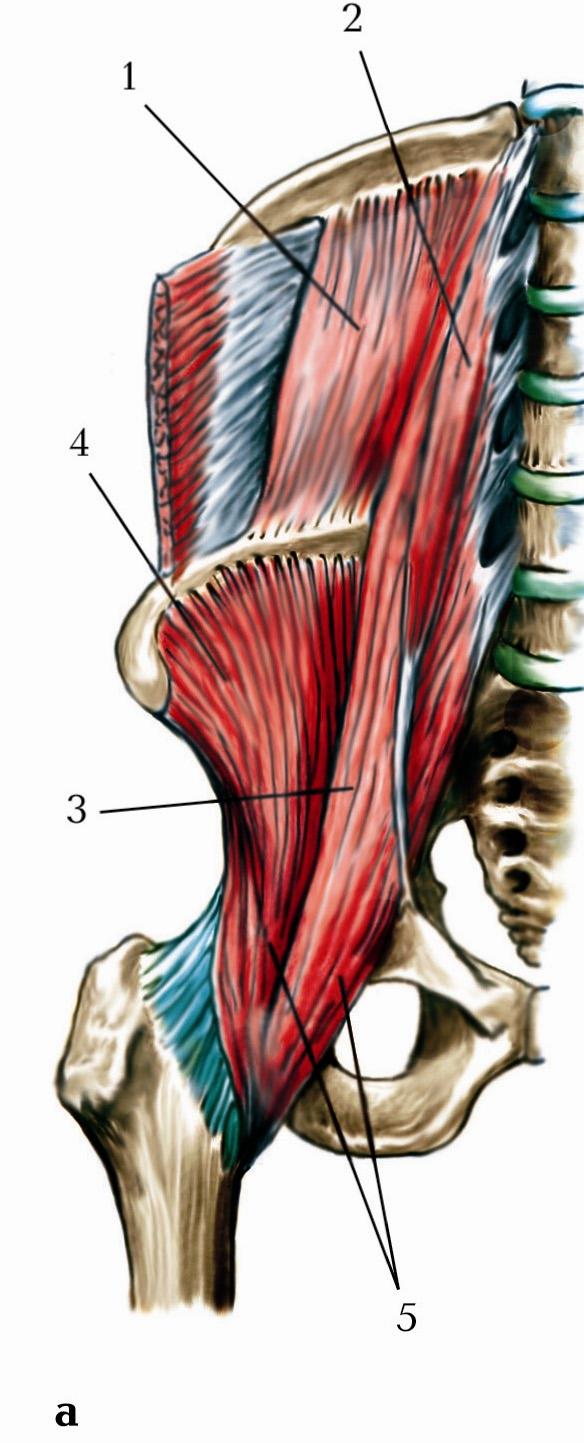

Анатомия мышц: Пириформис